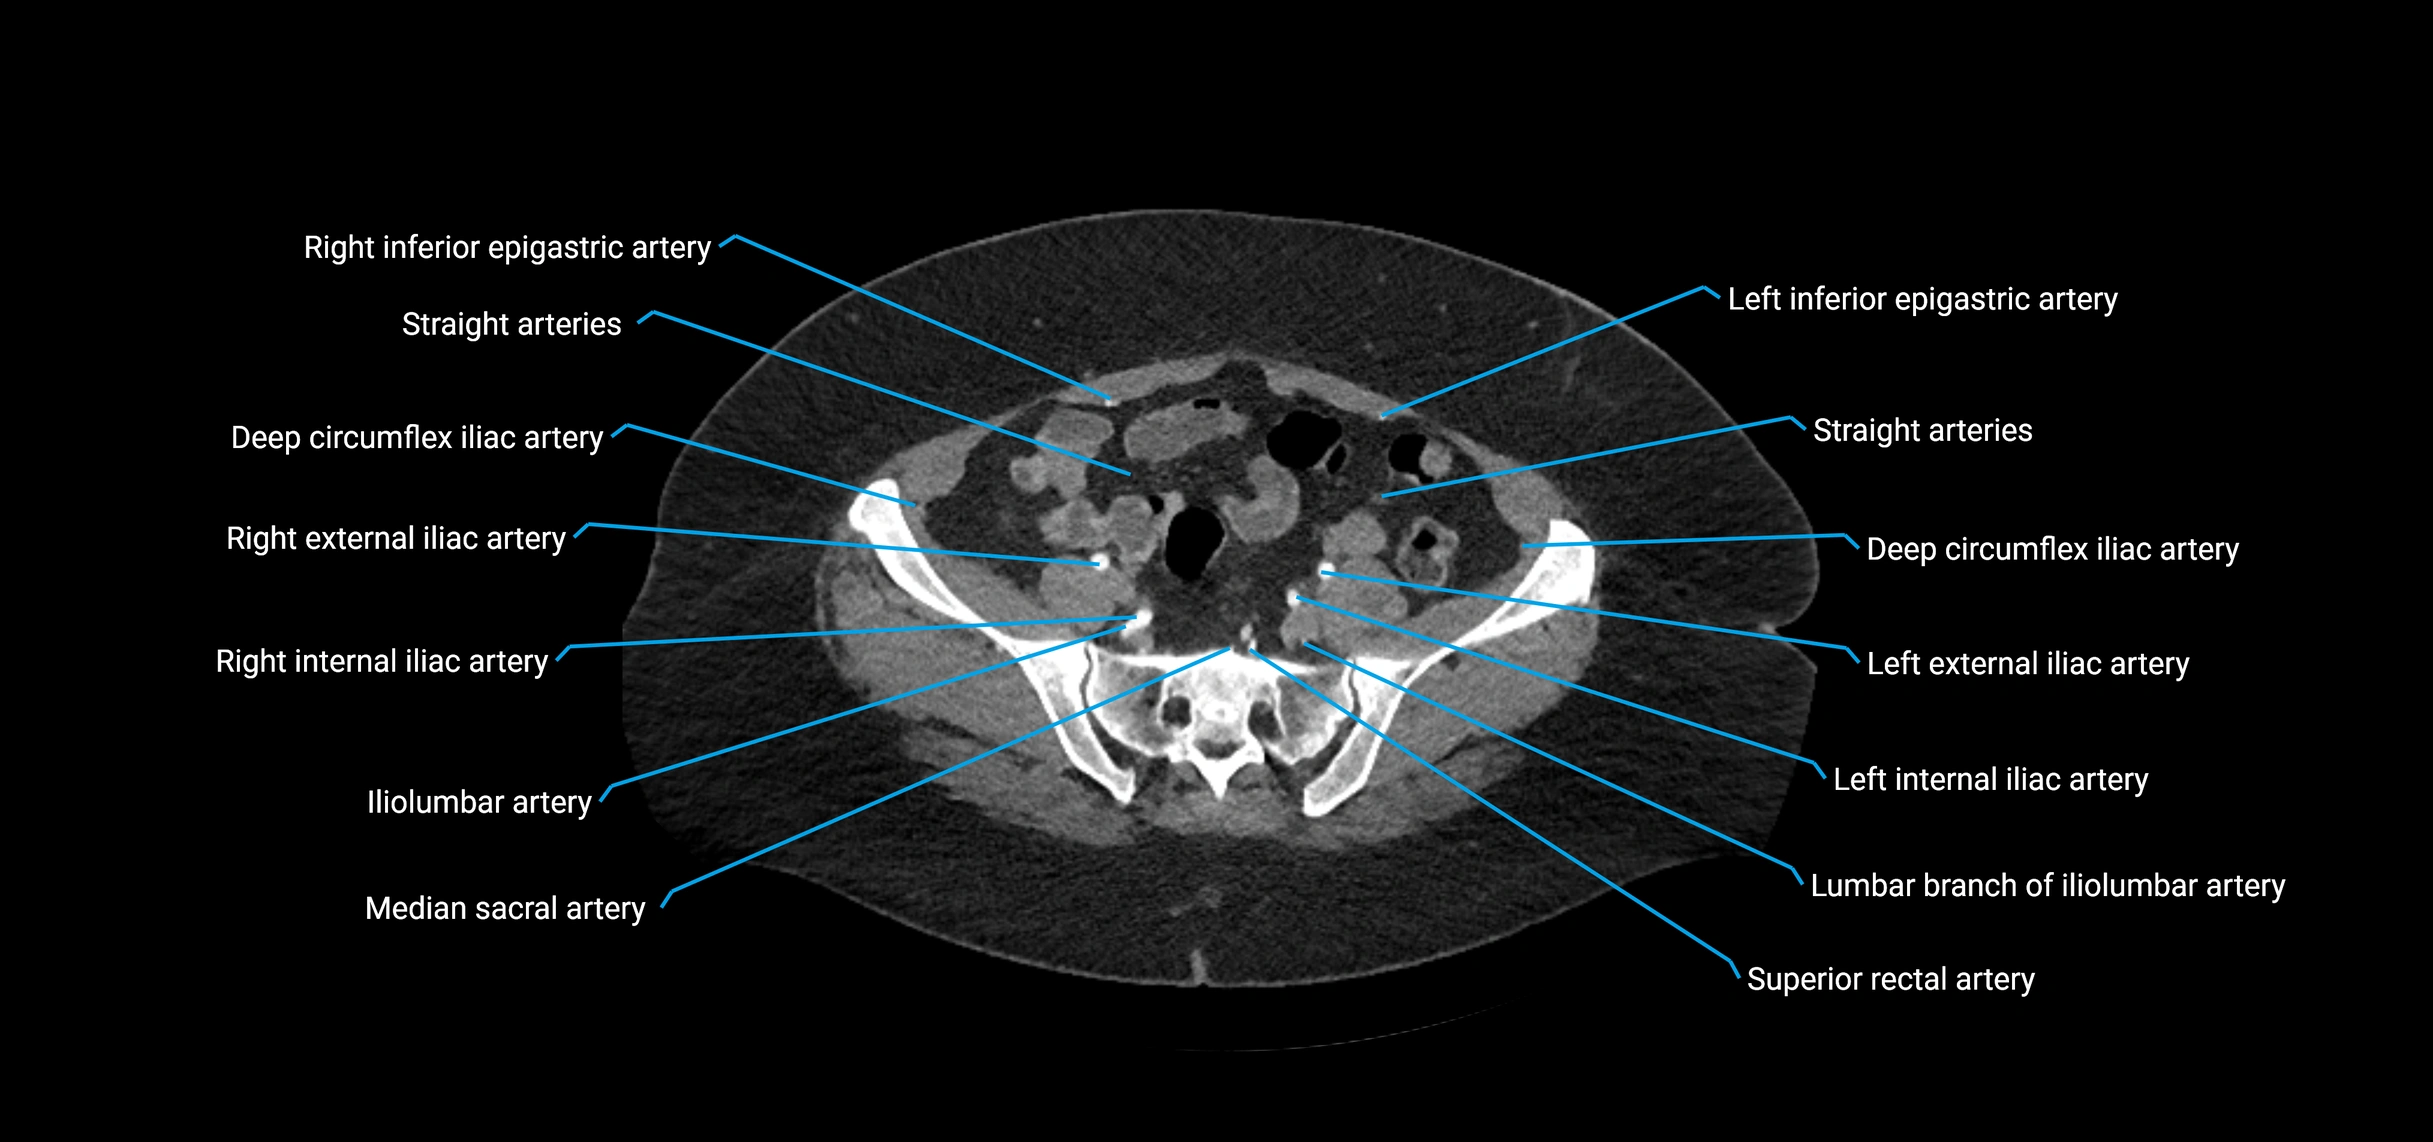

CT images

image

Contrast-enhanced CT (CTA):

• Gold standard for abdominal aortic imaging

• Provides excellent detail of lumen, wall, aneurysm, thrombus, and branch vessels

• Multiplanar and 3D reconstructions help in aneurysm measurement, stent graft planning, and dissection evaluation